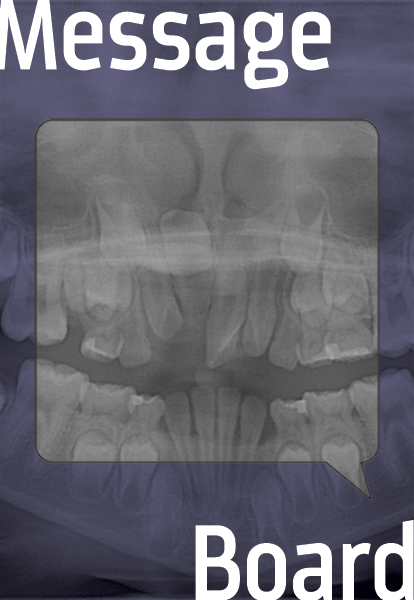

Inverted Impacted Teeth, Patience Is a Virtue

In this age of accelerated treatment done at the "right" time, some patients still need early evaluation, recall and extended care.